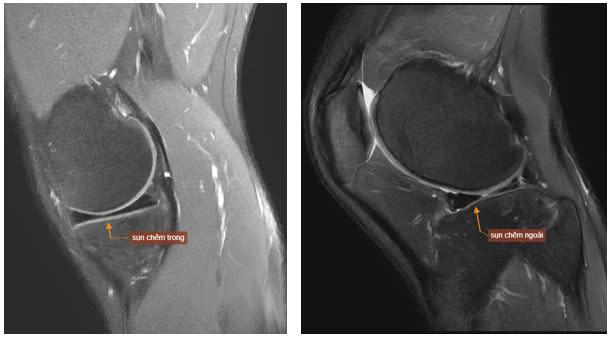

| Hình ảnh MRI khớp gối phải của bệnh nhân T.M.H cho thấy dấu hiệu rách quai xô. Ảnh BVCC |

Trên những hình ảnh cộng hưởng từ, bác sĩ và chuyên gia của Trung tâm chẩn đoán hình ảnh ghi nhận 5/6 dấu hiệu đặc trưng của rách quai xô điển hình: mất hình nơ sụn chêm, mảnh sụn rời trong khuyết gian lồi cầu, sụn chêm lật, hai sừng trước và sừng sau nhô bất thường. Hình ảnh cho thấy rách phức tạp ở thân và sừng sau sụn chêm ngoài, với mảnh sụn di lệch vào ổ khớp.